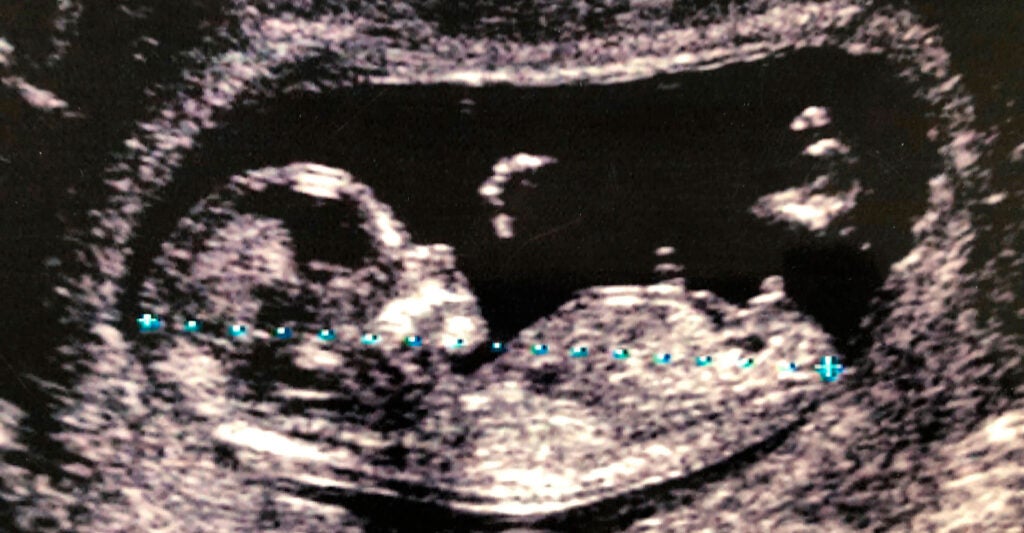

The New York Times’ analysis reported that positive results on prenatal genetic screenings can be wrong up to 85% of the time, and yet hundreds of thousands of those tests are performed annually.

That isn’t a trivial matter. Mothers presented with the far too common false positive DNA results face emotional trauma and agonizing decisions. As reported by the Times, some mothers receive a false positive, have an abortion, and then learn too late that their babies carried no risk of disease at all.

Dr. Diana Bianchi, the National Institutes of Health researcher quoted by the newspaper, published a peer-reviewed study in the New England Journal of Medicine in 2014, finding that for every 10 low-risk pregnant women screened for Down syndrome, at least five will be false positives with no risk of disease.

The numbers are even worse in low-risk women screened for Trisomy 18, which causes severe developmental delays due to an extra copy of chromosome 18: Six out of 10 women will receive false positives.

However, many mothers choose not to proceed with confirmatory testing and make their decision based solely on the often inaccurate genetic screenings. Nearly 70% of U.S. babies who test “positive” for Down syndrome in prenatal screenings are aborted.